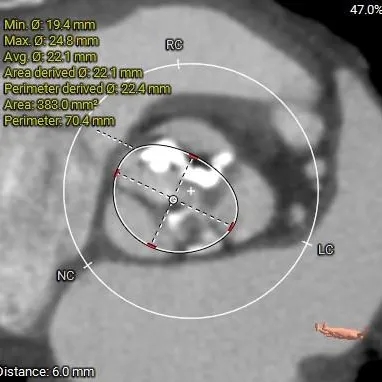

HU598:1225mm3

HU850:650mm3

Type1二叶式主动脉瓣(L-R),瓣叶增厚,极重度钙化,主要分布于无冠窦及右冠窦瓣叶,LVOT偏直筒型;